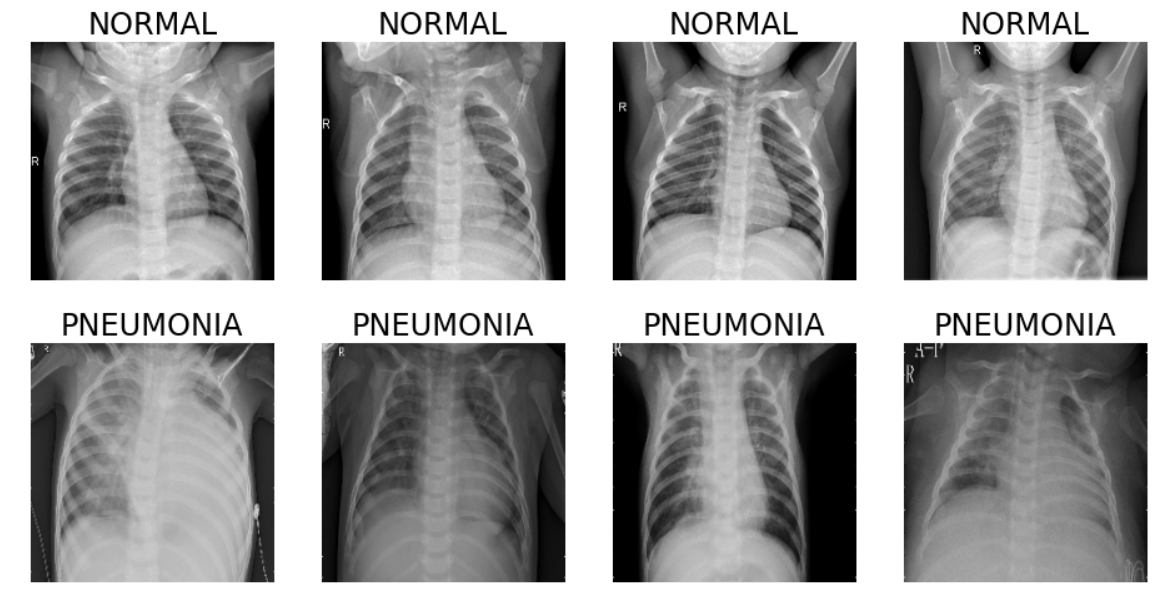

Due to the lack of benchmarks on DAL with label noise using multiple datasets for image classification, we run experiments on the following datasets: Chest X-ray Images (Pneumonia) [57], Food101 [58], CIFAR10 and CIFAR100 [59]. Table 2 below is a brief summary of each dataset. Figures 6(a) and 7(a) present sample image examples from each dataset.

Refer to caption

(a) Chest X-ray images showing four pneumonic and normal scans

Figure 7: Random images from the Chest X-ray of size 224 ×\times 224 (first four columns), and the more complex Food101 dataset images of size 512 ×\times 512